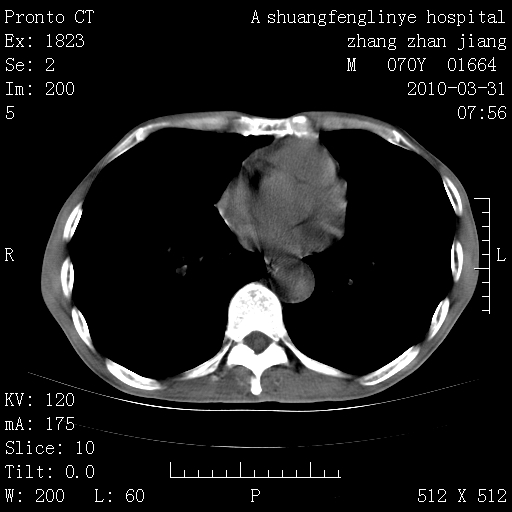

标题: CT25450:肺结核?

双上肺继发型tb并左上空洞形成,主动脉冠脉钙化。

支持:继发性肺结核伴空洞形成!建议纤支镜检查待出外周围型肺癌可能!

1)两肺上叶继发性肺结核并左肺上叶空洞形成。2)冠状动脉及主动脉钙化。